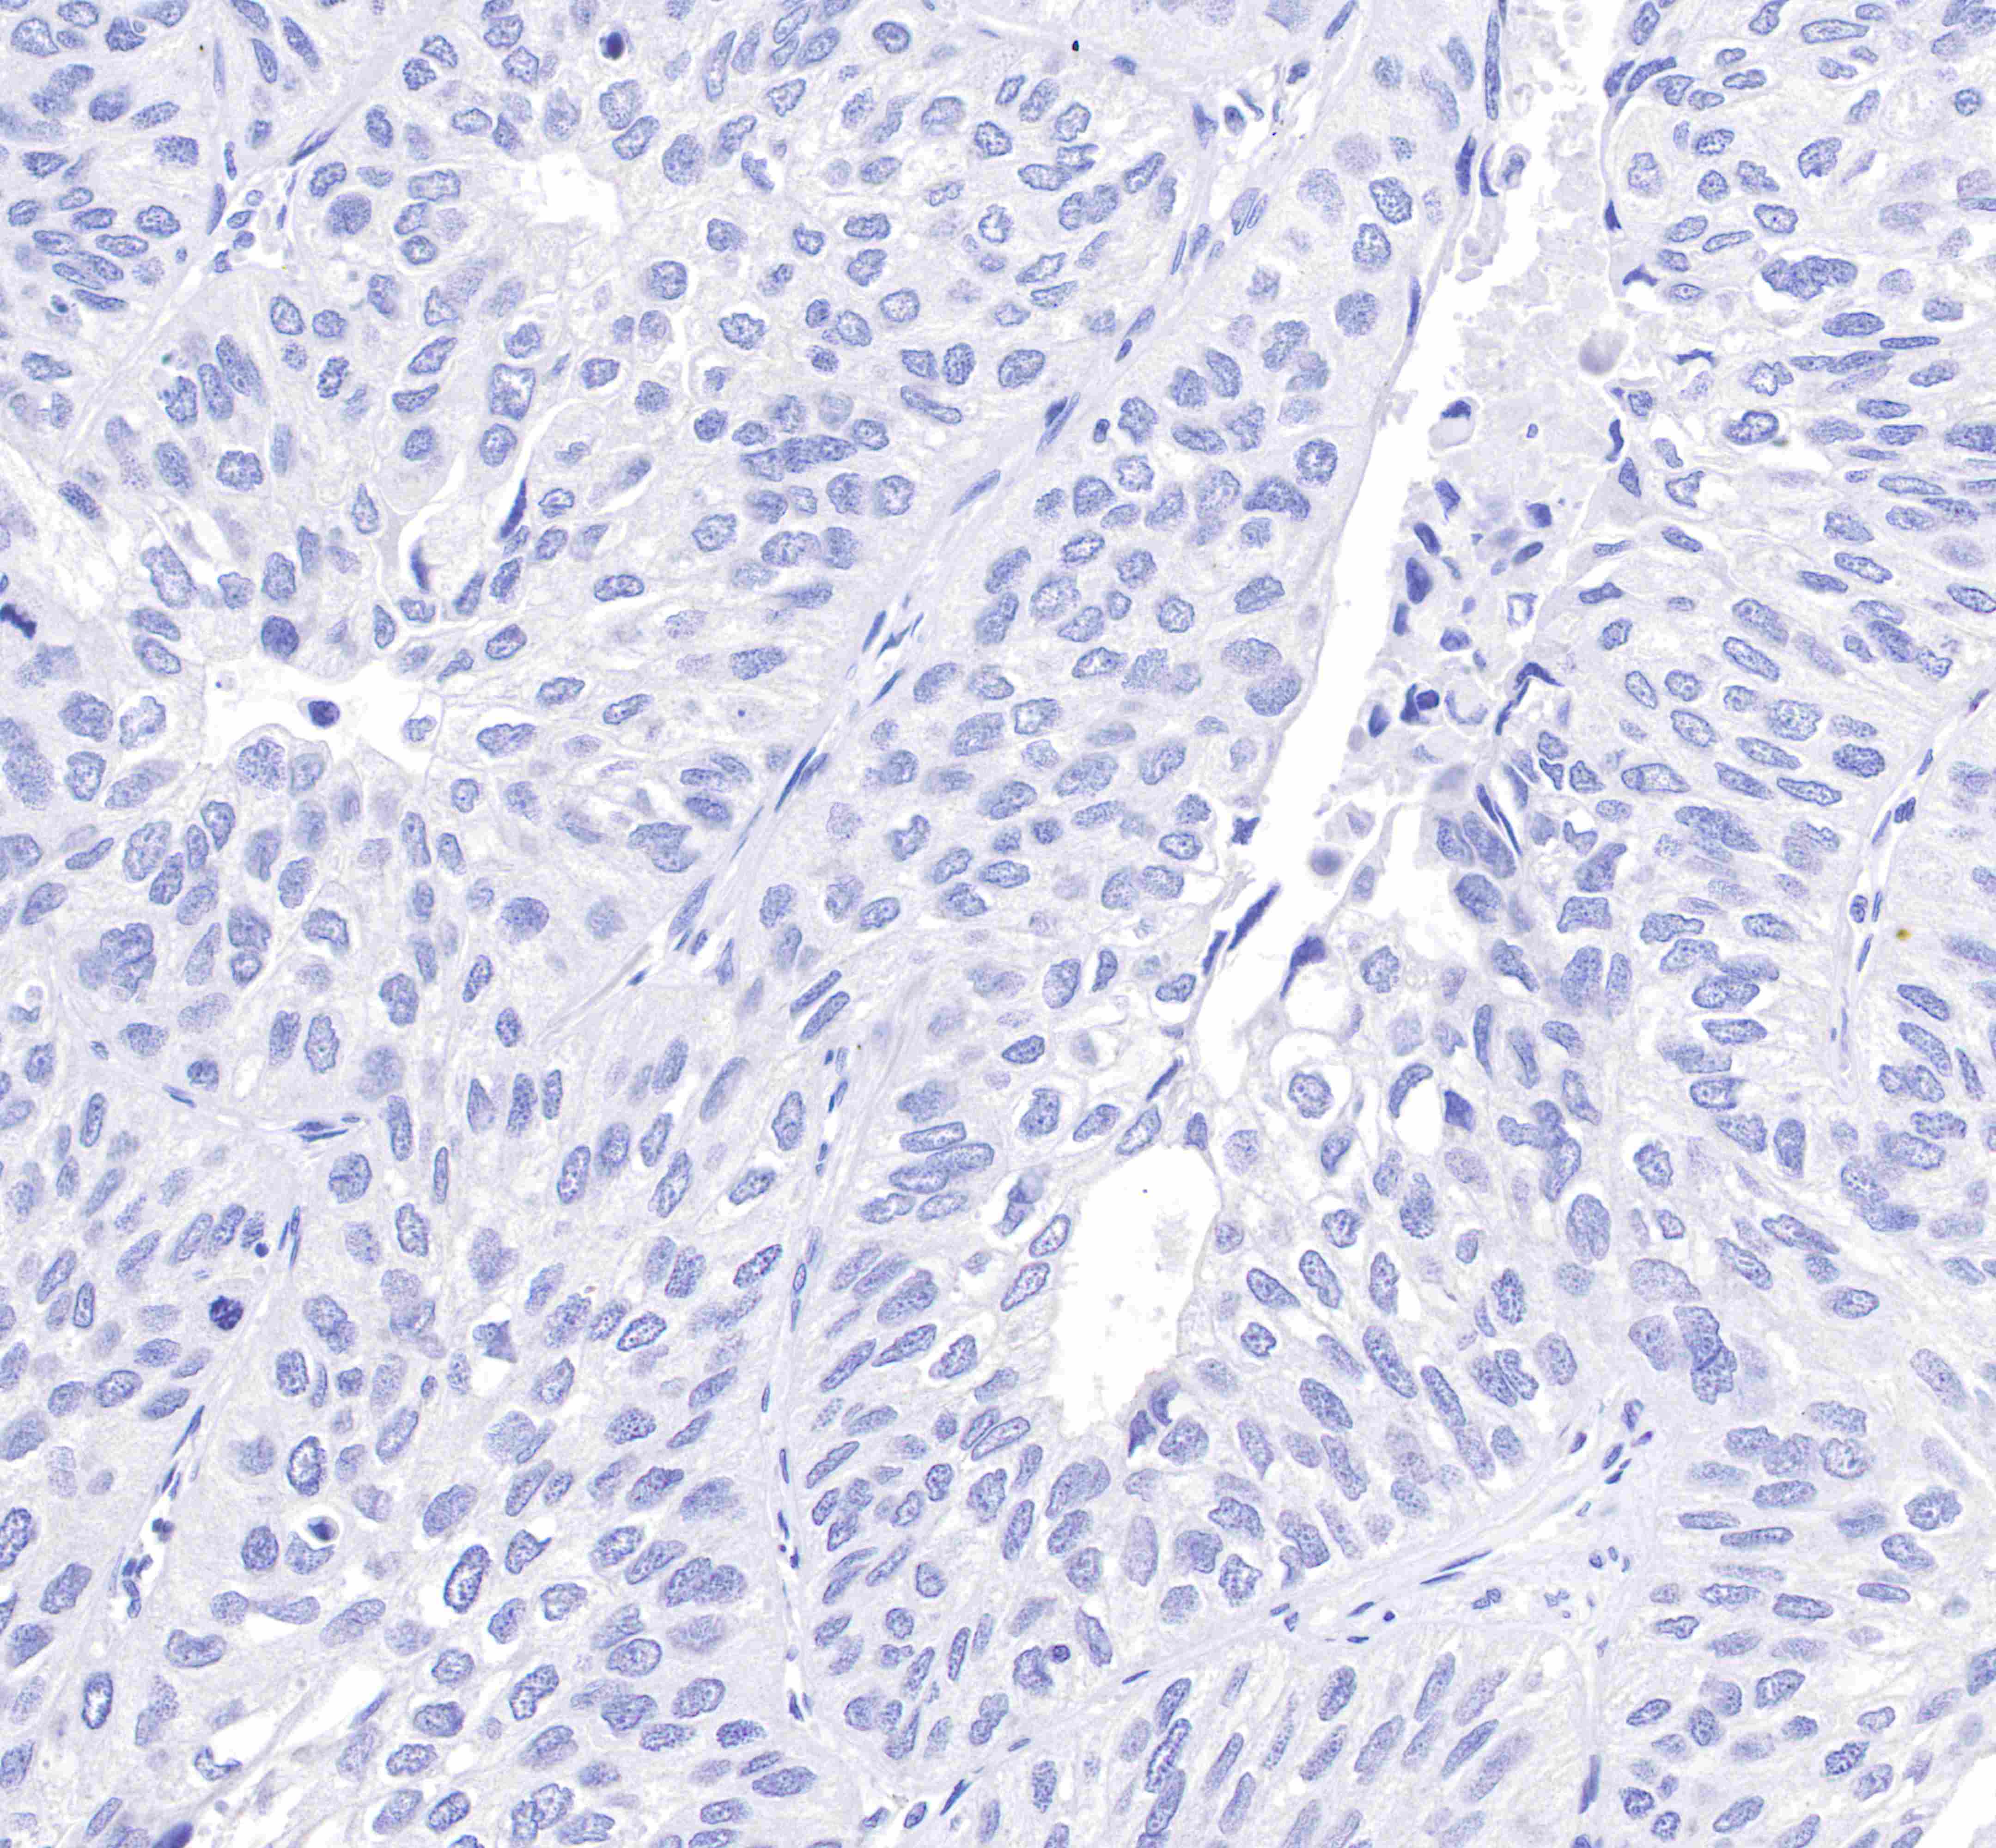

IHC shows negative staining in paraffin-embedded human lung squamous cell cancer (negative tissue).

Anti-GCDFP-15 antibody was used at 1:100 dilution, followed by a Goat Anti-Rabbit IgG H&L (HRP) ready to use.

Counterstained with hematoxylin.

Heat mediated antigen retrieval with Tris/EDTA buffer pH9.0 was performed before commencing with IHC staining protocol.